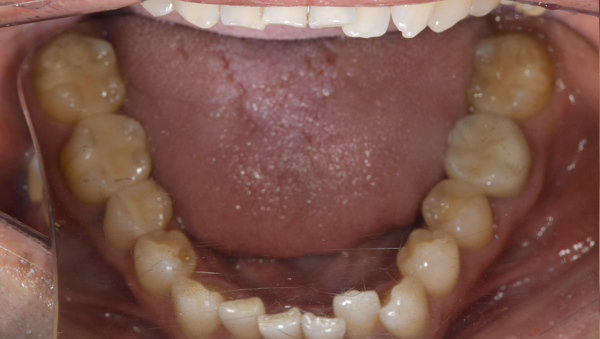

治療前:下の歯

担当医師所見:

下顎右側臼歯部には一見大きな問題はないように見えるが、 頰側にフィステルと言われる排膿路があり発赤と主張があり炎症状態が続いていた。

治療後:下の歯

下顎右側第1大臼歯は抜歯後、仮歯に置き換え治癒を待った後ジルコニアステイニングBrにて補綴。 全顎的に色調・形態共に調和がとれている。